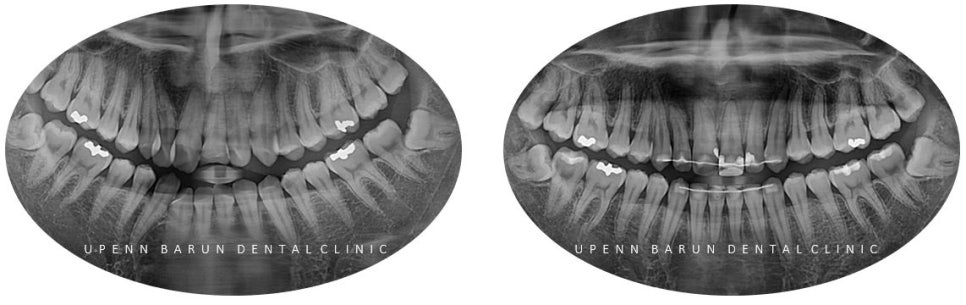

위의 주소로 내원해주신 환자분께서는 부러진 앞니치료와 함께 교정치료를 하고 싶어하셨는데요

교정치료 전 엑스레이 촬영 결과

앞니 사이사이에 충치가 있을뿐만 아니라

위앞니가 부러져 있는 상태였어요 ㅠㅠ

5년전에 떼웠던 부위 이기도 하고 범위가 워낙 커서

타치과에서는

'신경치료 후 씌워야 한다' 는 얘기를 듣고 오셨는데요 T^T

충치와 파절된 부위가 생각보다 커서

신경치료의 가능성이 높았지만

교정치료 전에

'신경치료를 하지 않고 ' 보존적으로 레진치료로 마무리 해드렸습니다.